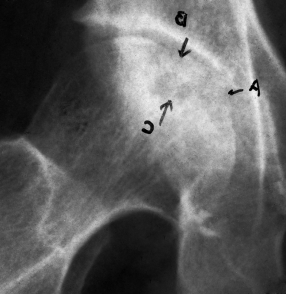

病例1男,29岁,患病2年,治疗15个月痊愈。治疗前,股骨头顶部塌陷、变平,顶部可见大块坏死骨,密度增高(a)。经过9个月的治疗,死骨与正常骨融合,密度减低,表面不清楚(b)。治疗后,股骨头略平,骨密度均匀,骨小梁清晰(c)

Case 1 male, 29 years old, 2 years sick, 15 months after eating. Before eating, the top of the femoral head collapsed, flattened, the top of the large dead bone, increased density, uneven thickness (a). After 9 months of treatment, the dead bone fused with the normal bone, the density decreased and the surface was unclear (b). After eating, the femoral head is slightly flat, the bone density is even, and the bone trabecula is clear (c).